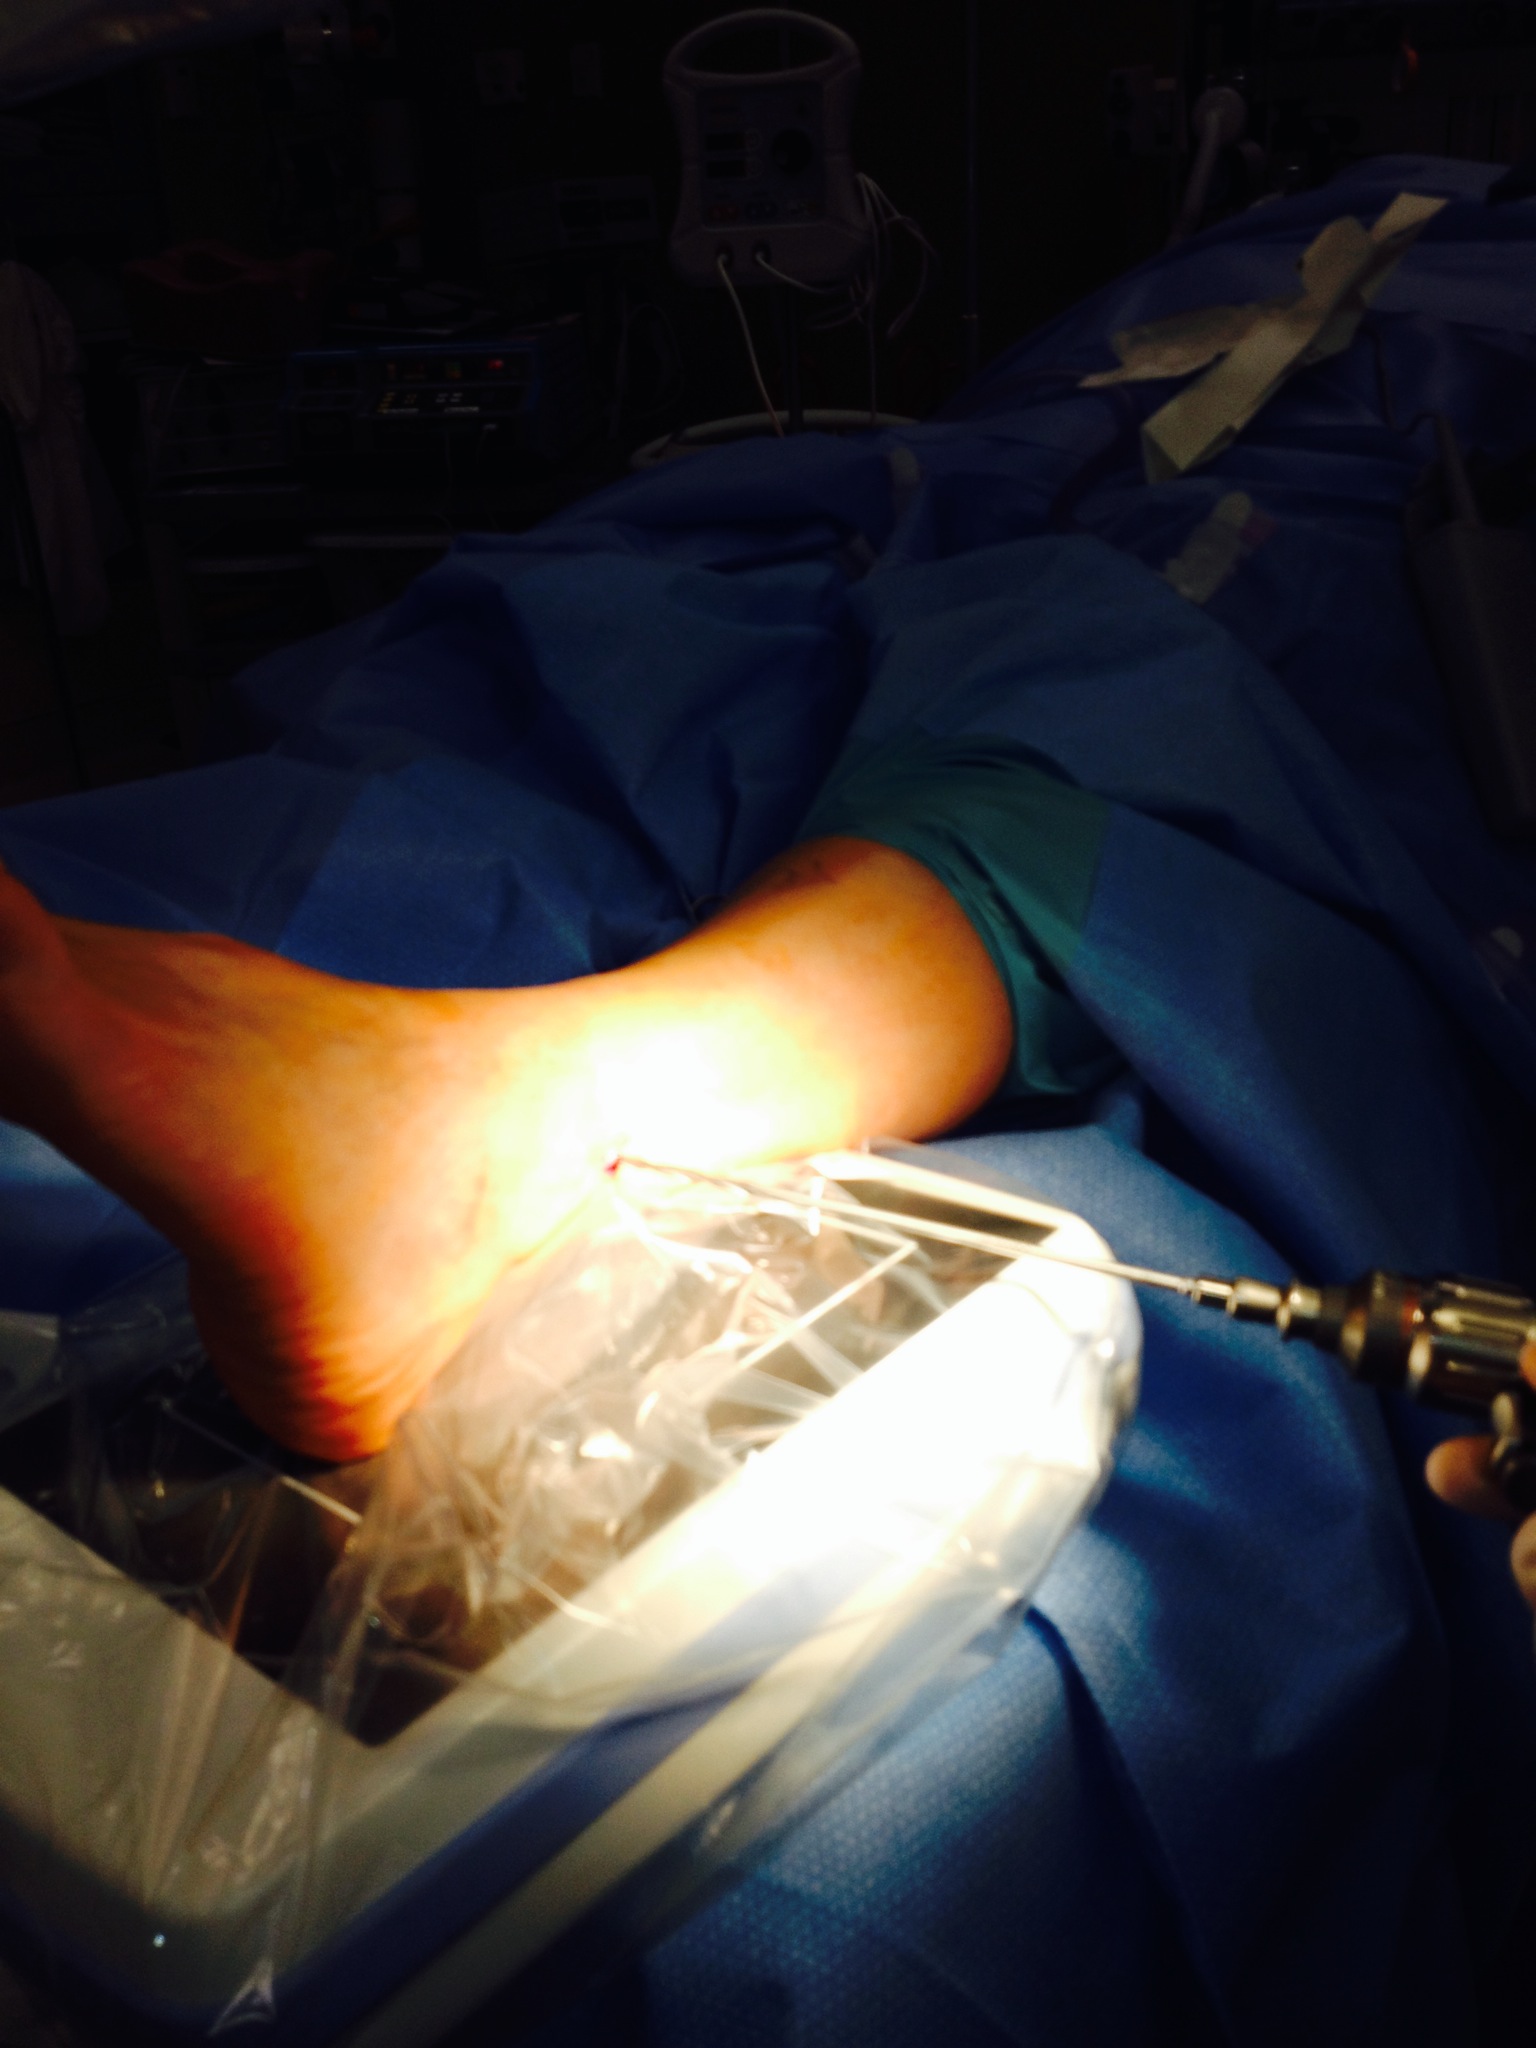

Here are photos (click on the photos to enlarge) taken during the Arthrex TightRope Dynamic Stabilization Surgery. I consider this surgery to be very minimally invasive. Only a couple of stitches in my lateral ankle/fibula bone. I was just a little over an hour and my husband was able to see me in recovery. I woke up as usual with no complications and I began my usual hunger spree of “Feed Me”. I did remember saying, “Why do I have to wake up, I don’t want too because I really didn’t want to face the reality of life in a non weight bearing status again.” For me surgery has always been the easy part. Life afterwards is the struggle.